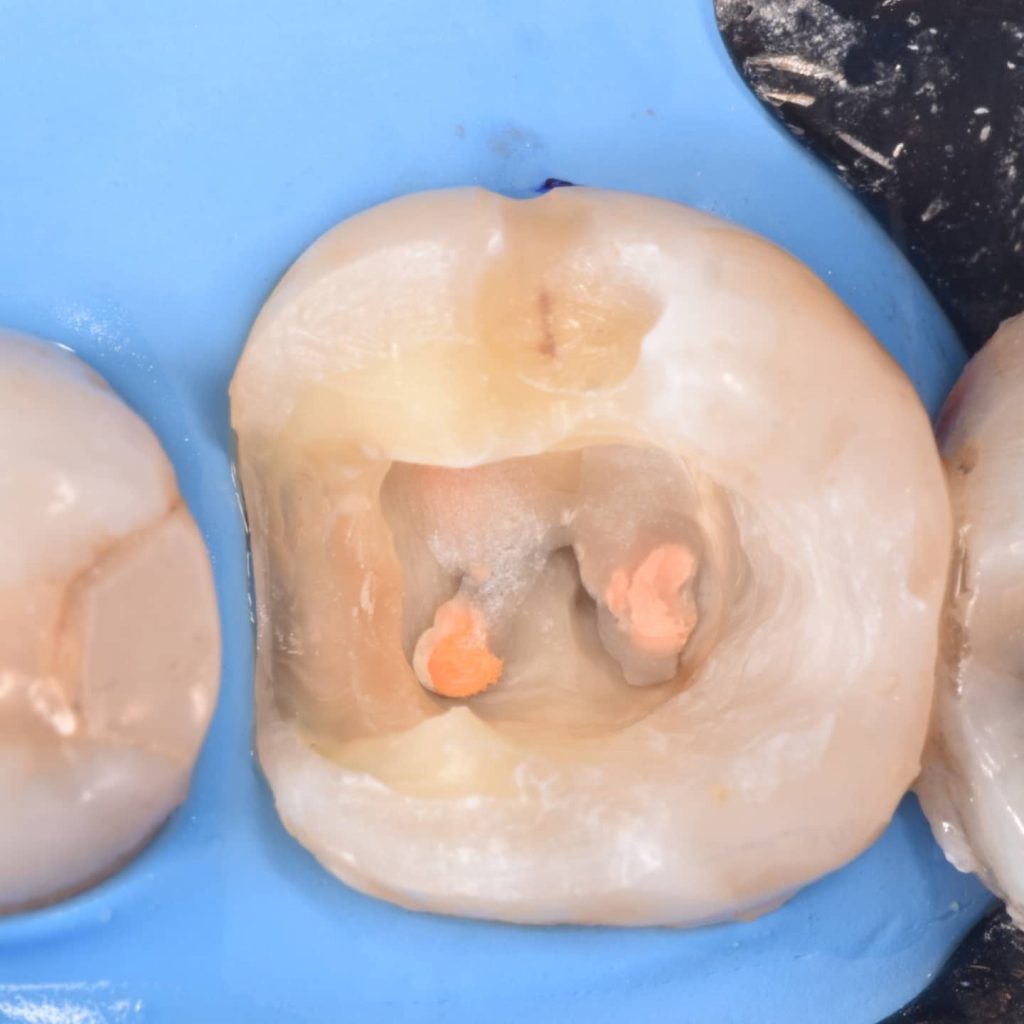

After 6 month of endo treatment the pateint come to complete the final filling as you see the amalgam mesaily should removed

Amalgam removal

Ever x posterior for more support to the filling and for dentin replacement